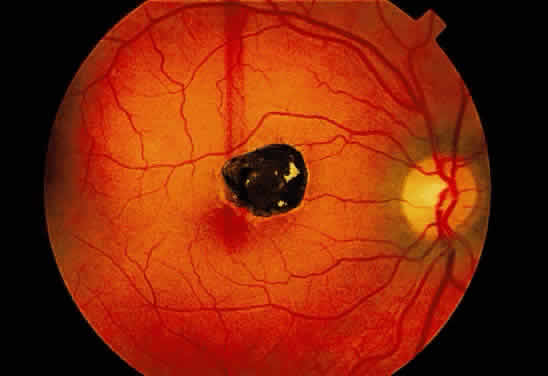

no such delineating structure is present. Therefore, a fresh

nerve fiber layer hemorrhage appears bright red and has feathery

borders, whereas a subpigment epithelial hemorrhage appears brown-black

Fig. 13. A. Fundus photograph of a subpigment epithelium hemorrhage superotemporal

to the disc secondary to a macroaneurysm. Notice its dark color and sharp

border. The central portion of the hemorrhage has extended through

the sensory retinal to the subinternal limiting membrane area. B. Fluorescein angiography showing the retinal vessels overlying the deep

hemorrhage but obscured by the central extension anteriorly. (B, courtesy of William Tasman, MD, Philadelphia, PA) Fig. 13. A. Fundus photograph of a subpigment epithelium hemorrhage superotemporal

to the disc secondary to a macroaneurysm. Notice its dark color and sharp

border. The central portion of the hemorrhage has extended through

the sensory retinal to the subinternal limiting membrane area. B. Fluorescein angiography showing the retinal vessels overlying the deep

hemorrhage but obscured by the central extension anteriorly. (B, courtesy of William Tasman, MD, Philadelphia, PA)